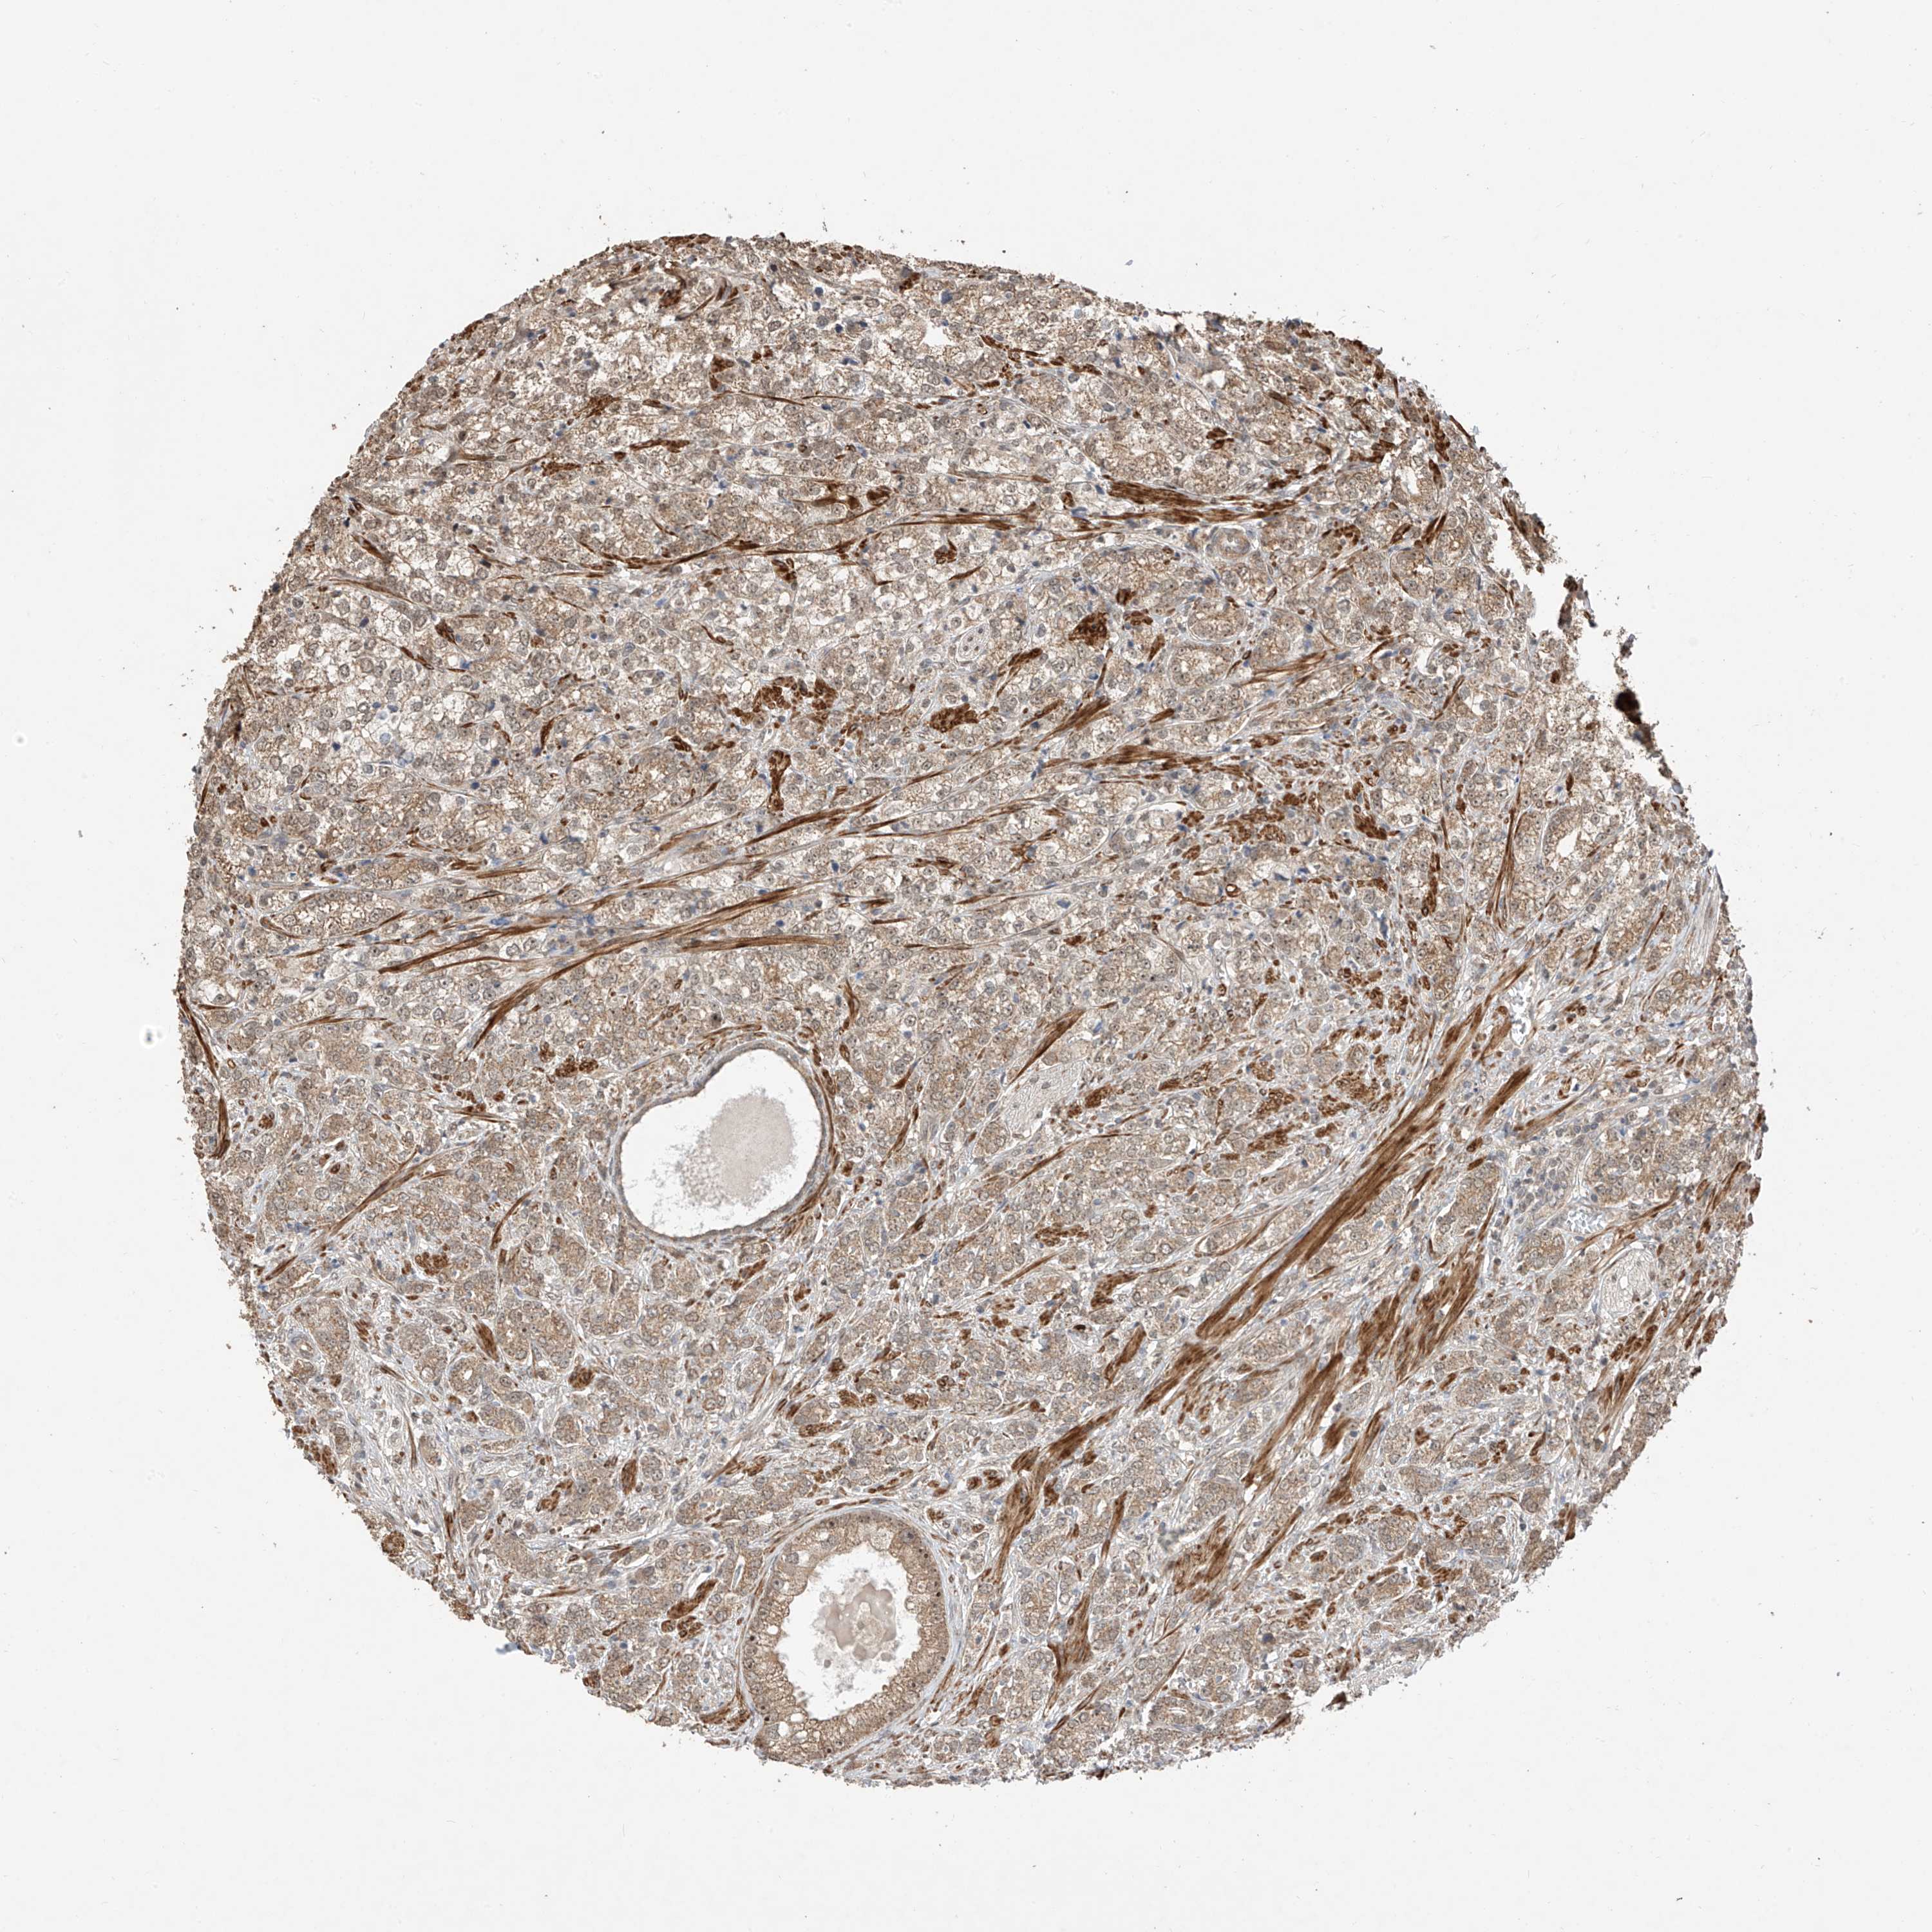

PROSTATE CANCER - Protein expressioni

A mouse-over function shows sample information and annotation data. Click on an image to view it in a full screen mode. Samples can be filtered based on level of antibody staining by selecting one or several of the following categories: high, medium, low and not detected. The assay and annotation is described here.

Antibody stainingi

Antibody staining in the annotated cell types in the current human tissue is reported as not detected, low, medium, or high, based on conventional immunohistochemistry profiling in selected tissues. This score is based on the combination of the staining intensity and fraction of stained cells.

Each image is clickable and will lead to virtual microscopy that enables deeper exploration of all samples and also displays staining intensity scores, fraction scores and subcellular localization as well as patient and tissue information for each sample.

Antibody HPA031804

Staining

High

Medium

Low

Not detected

Intensity

Strong

Moderate

Weak

Negative

Quantity

>75%

75%-25%

<25%

None

Location

Nuclear

Cytoplasmic/membranous

Cytoplasmic/membranous,nuclear

Adenocarcinoma, NOS

Adenocarcinoma, High grade

Adenocarcinoma, Low grade